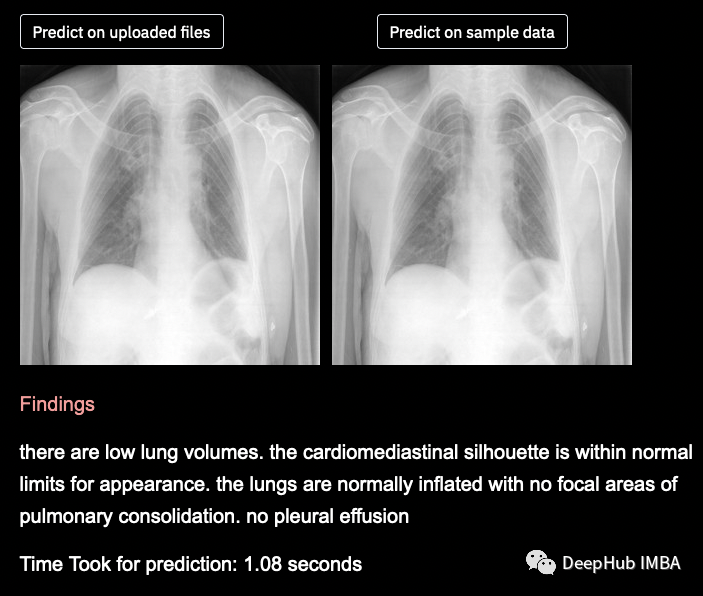

图像描述是生成图像文本描述的过程。它使用自然语言处理和计算机视觉来为图像生成描述的文本字幕。一幅图像可以有很多个不同的描述,但是只要它正确地描述了图像,并且描述涵盖了图像中的大部分信息就可以说是没问题的。下面是示例图片和生成的描述文字。

使用Greedy Search测试标题预测和BLEU评分

为什么只有28.3%的BLEU得分。这时深度学习需要大量的数据,但我们提供给模型的数据非常少,即使在大量重采样之后,也会偏向于非疾病数据,因此这个BLEU评分对于我们使用的数据来说已经很好了,如果我们有大量的数据,那么相同的模型将表现得非常好,并给出更好的结果。

预测是有意义的,模型能够预测疾病和非疾病数据。为了提高模型的性能,我们需要更多的数据,以便我们的模型训练得更好,给出更好的输出。

我们能够成功地为x射线图像生成标题(发现),并能够通过带有GRUs的基于全局注意力的编码器-解码器模型实现约28.3%的BLEU评分。由于我们拥有的数据非常少,而且偏向于非患病数据,我们无法获得非常好的BLEU得分,但如果我们有大量平衡的数据,那么同一段代码可以非常好地预测图像的标题。